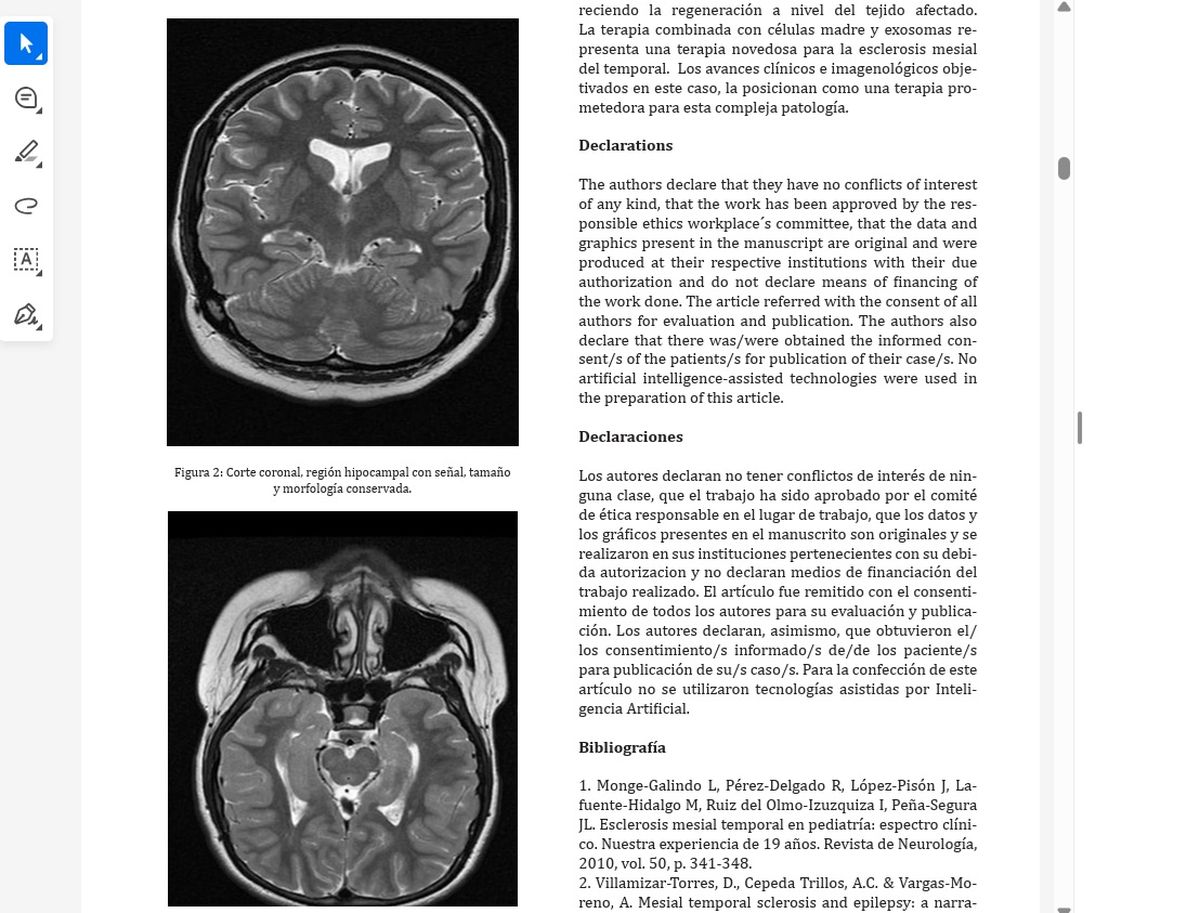

En conjunto, se observa una maduración cognitiva, emocional y social progresiva; manifestando un perfil evolutivo notablemente más adaptado y funcional. Todos estos avances encuentran su correlato en la resonancia magnética del 27/6/25 en donde se objetiva el comienzo dela regeneración a nivel de la región hipocampal, dicha imagen fue informada como normal.